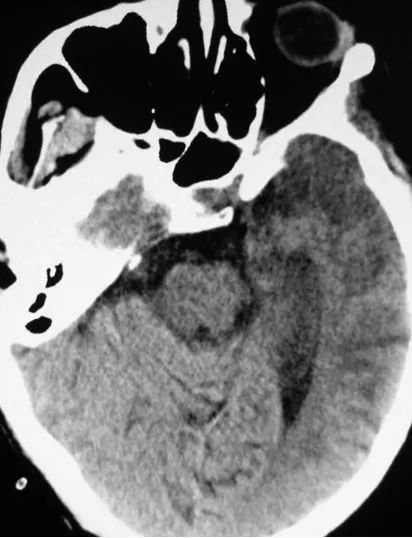

住院后检查:头颅CT,左侧颞叶大片低密度影;